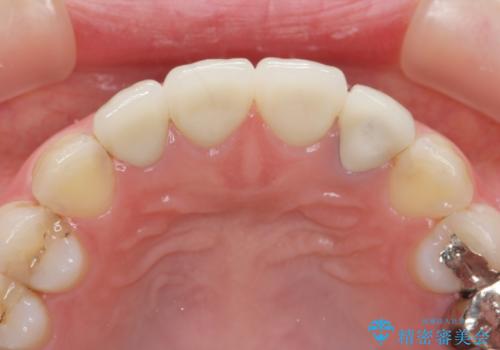

- 37万円(仮歯×3・ファイバーコア×2・ジルコニアクラウン×3)費用は治療当時の料金となります

審美的なジルコニアクラウンを装着し、審美性が回復されたと満足いただくことができました。